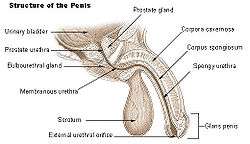

The secretory epithelium is mainly pseudostratified, comprising tall columnar cells and basal cells which are supported by a fibroelastic stroma containing randomly oriented smooth muscle bundles that's continuous with the bladder. The epithelium is highly variable and areas of low cuboidal or squamous epithelium are also present, with transitional epithelium in the distal regions of the longer ducts.[8] Within the prostate, the urethra coming from the bladder is called the prostatic urethra and merges with the two ejaculatory ducts.[9]

During male ejaculation, sperm is transmitted from the vas deferens into the male urethra via the ejaculatory ducts, which lie within the prostate gland. It is possible for some men to achieve orgasm solely through stimulation of the prostate gland, such as prostate massage or receptive anal intercourse.[18][19][20]

Urinary bladder Structure of the penis

Structure of the penis Lobes of prostate

Vesiculae seminales and ampullae of ductus deferentes, front view. Vertical section of bladder, penis, and urethra.

Vertical section of bladder, penis, and urethra. Dissection of prostate showing prostatic urethra.